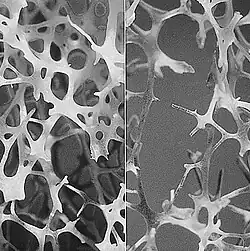

TBS (Trabecular Bone Score)

normale (à gauche) et dégradée (à droite)

Concernant la micro-architecture, des structures osseuses plus ou moins résistantes mécaniquement peuvent exister (peu de grosses travées ou une myriade de travées fines plus solide mécaniquement). En effet, la perte de masse osseuse s’accompagne souvent d’une détérioration de l’architecture osseuse, traduite par une diminution du nombre des travées d’os spongieux par amincissement, un accroissement des distances inter-trabéculaires, ainsi qu’une perte de connectivité du réseau trabéculaire, ceci conduisant à un os plus « poreux » et plus fragile.

Selon MedImaps et des articles publiés par les chercheurs associés à MedImaps, TBS iNsight est le reflet de l’état structurel de la micro-architecture osseuse. TBS iNsight est fortement corrélé au nombre de travées et à leur connectivité et négativement à l’espace séparant deux travées[1],[2]. C'est-à-dire qu’une forte valeur TBS iNsight signifierait que la micro-architecture osseuse est dense et très connectée avec peu d’espace entre les travées. A contrario, une faible valeur de TBS iNsight signifierait que la micro-architecture osseuse est lacunaire et peu connectée avec de grands espaces entre les travées[3].